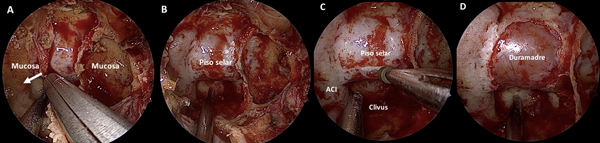

Se procede a la apertura del rostrum esfenoidal, la cual debe ser siempre amplia. Muchas veces es esto lo que proporciona un adecuado surgical freedom y no la amputación de estructuras nasales. Luego, se resecan todos los septos intrasinusales y se exentera la mucosa a fines de exponer con claridad todos los reparos anatómicos: la prominencia del piso de la silla turca al centro, la silueta de ambas arterias carótidas internas a los lados, el planum esfeno-etmoidal arriba y el clivus abajo (Figura 4 A-B).

Figura 4. Tiempo intrasinusal. A-D: exposición de la duramadre selar.

En la fase selar la pared posterior del seno esfenoidal (i.e la prominencia selar) es fresada con punta diamantada a fines de disminuir su espesor (Figura 4C). Luego, se realiza una apertura “a medida” utilizando una pinza de Kerrison N°1. El plano dural queda expuesto hasta evidenciarse los “cuatro azules” o la “corona azul” (i.e. el limite más medial de ambos senos cavernosos y el límite de ambos senos intercavernosos)14 (Figura 4D).